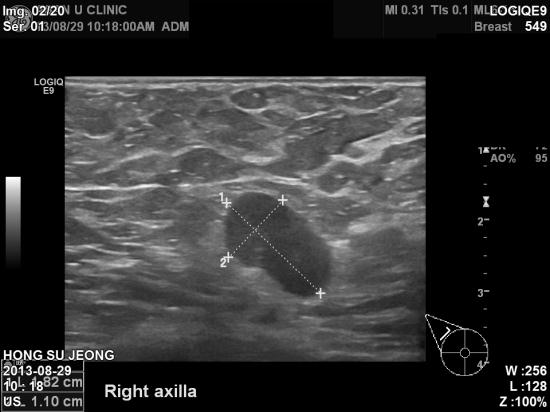

아산유외과 개원 후 21번째 유방암 진단.

3년동안 있던 유방에 혹이 피부바깥을 튀어나오며

커져 내원하셨다는 만 59세 여자분입니다.

조직검사로 우측 유방암의 피부, 우측 겨드랑이 전이를 확인하고

서울 아산병원전원하였습니다.